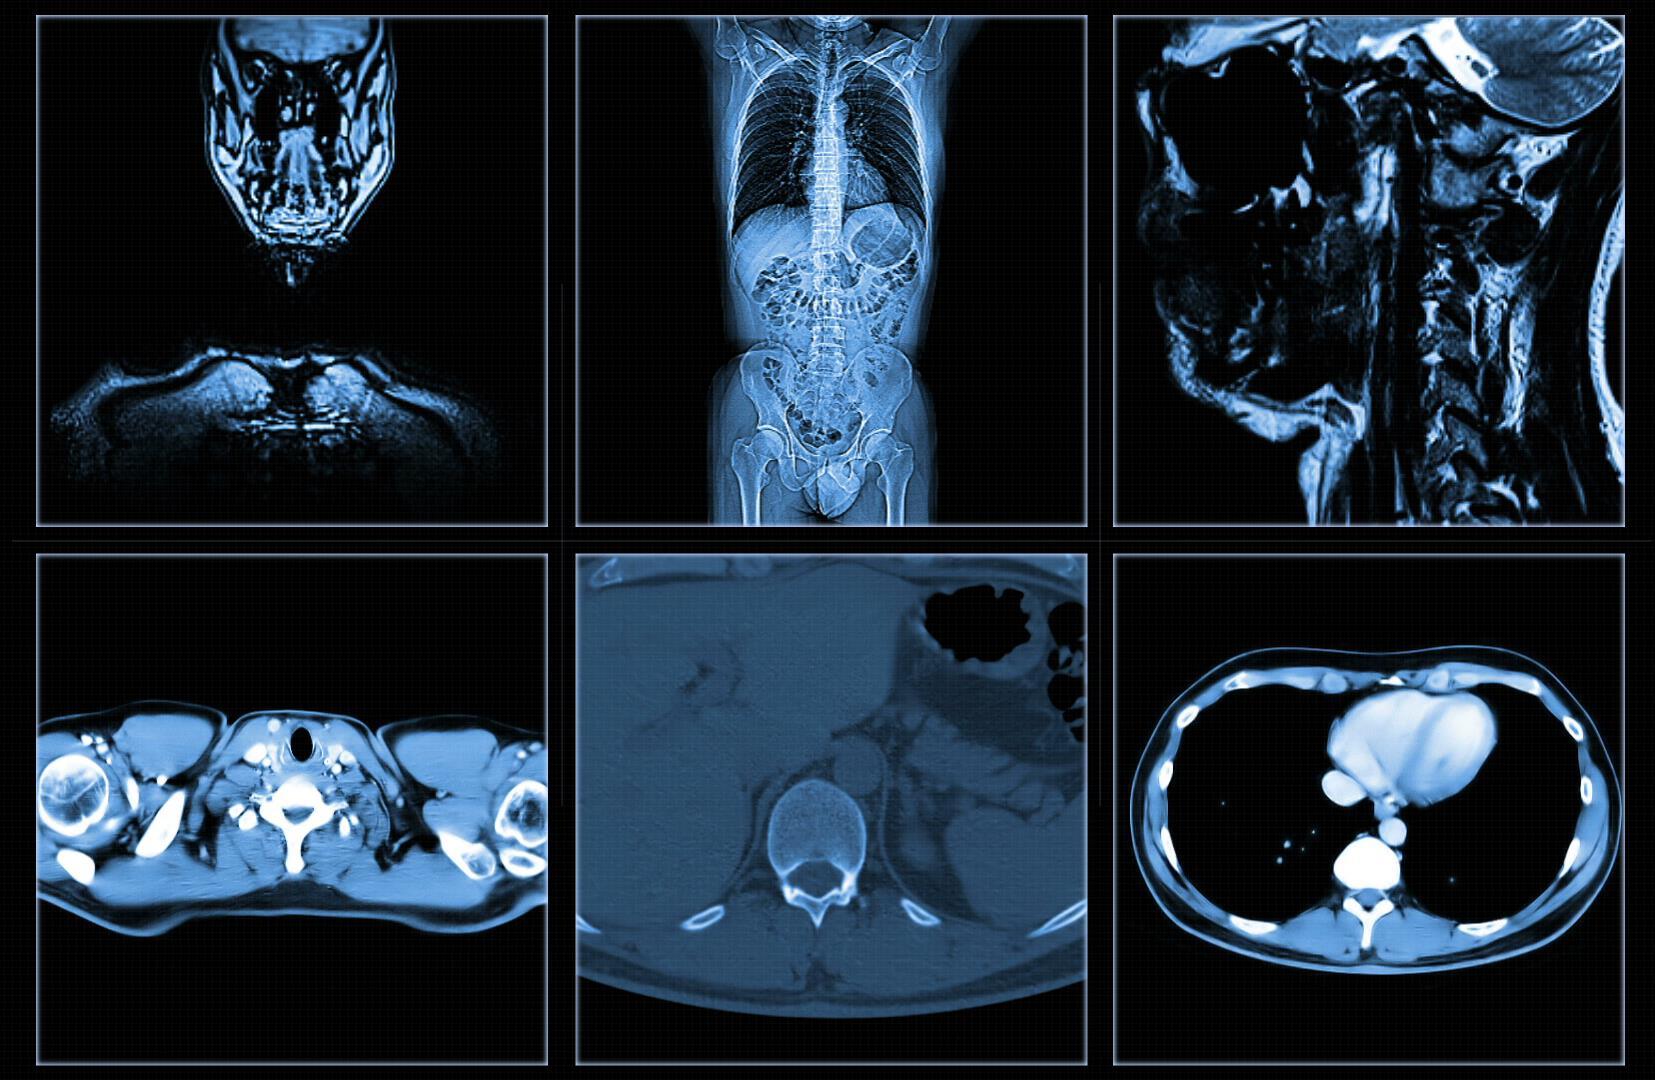

Imaging tests create pictures of areas inside your body that help the doctor see whether a tumor is present. These pictures can be made in several ways.

• X -ray

• Ultrasound

• Computed Tomography (CT)

• Magnetic Resonance Imaging (MRI)

• Nuclear scan

• Bone scan

• PET scan

• X-rays use low doses of radiation to create pictures of the inside of the body.

• Chest radiographs and mammograms are often used for early cancer detection.

• Risks:

• Radiation risk to you as a patient is similar adding 10 days of natural exposure or smoking a few cigarettes.

• allergic reactions to the contrast agent

• Mammography has been shown to decrease the risk of dying from breast cancer by detecting it earlier when it is usually easier to treat.

• Obtain a baseline chest x-ray Repeat chest x-rays every 5 years or sooner if medically indicated

• Cost $100 - $400

• A computed tomography scan CT scan, or CAT scan uses computer-controlled X-rays to create images of the body

• More vivid than a plain X-ray.

• May be given a contrast agent to more clearly show the boundaries between organs and potential tumors.

• Radiation risk to you depends on the amount of body scanned and can range from the equaling of 2 months to 10 years of background radiation.

• CT scans are effective means of screening for colorectal and lung.

• Low-dose Helical Chest CT (LDCT) starting at age 50 is recommended for firefighters.

• Findings need follow up and additional testing or a biopsy which come with additional risk.

• Low Dose Lung CT is being used in several studies on firefighter cancer and cardiac risks and the benefit.

• Uses radio waves in the presence of a strong magnetic field that surrounds the opening of the MRI machine where the patient lies to get tissues to emit radio waves of their own.

• Different tissues emit a signal based on their chemical makeup, so a picture of the body organs is created.

• Generally Safe — so long as there is no metal in your body, there is no harmful radiation.

• The use of whole-body MRI is not recommended in asymptomatic patients who don’t have a genetic predisposition for cancer.

• Cost $400 - $12,000

• Varying rates of false positive results, additional testing can be resource exhaustive.

• Without the use of contrast in the MRI, it can overlook several cancers including colon, thyroid, and breast.